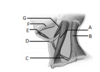

Identify the structures labelled A-G

A- Sternocleidomastoid

B- Trapezius

C- Omohyoid

D- Hyoid

E- Anterior belly of digastric

F- Mandible

G- Posterior belly of digastric